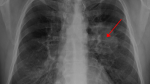

8 dấu hiệu cảnh báo UNG THƯ PHỔI đang sống trong cơ thể, nên biết sớm kẻo hối hận

Ung thư phổi là một trong những căn bệnh ung thư nguy hiểm. Bệnh nhân bị ung thư phổi có tỷ lệ sống sót rất thấp. Dưới đây là 8 dấu hiệu cảnh báo ung thư phổi sớm nhất.